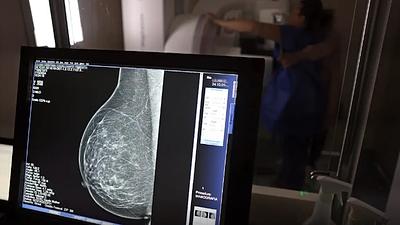

examecancermama.jpg

Cerca de 77 mil mulheres aguardam mamografia pelo SUS, diz relatório

31/10/2024, 14:02

Segundo a instituição, em alguns locais do país, o tempo de espera por uma mamografia na rede pública pode chegar a 80 dias. O exame, quando realizado em tempo hábil, permite a detecção precoce de alterações mamárias.